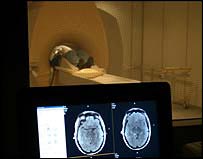

Tomografia do cérebro

Participantes tiveram sua atividade cerebral monitorada

Cientistas da University College London monitoraram a atividade cerebral de um grupo de voluntários enquanto estes observavam pessoas de quem gostavam e não gostavam sendo fisicamente castigadas.

Na fase seguinte, os atores simularam receber choques elétricos enquanto os voluntários tinham sua atividade cerebral monitorada.

Quando os atores "honestos" receberam choques, homens e mulheres apresentaram aumento da atividade cerebral nas regiões do cérebro associadas à dor.

Quando o ator "desonesto" recebeu um choque, as mulheres apresentaram respostas semelhantes de empatia.

Os homens, porém, não mostraram sinais de empatia ao ver o ator "desonesto" sendo castigado.

Pelo contrário, os voluntários do sexo masculino apresentaram aumento de atividade na região do cérebro associada ao prazer.